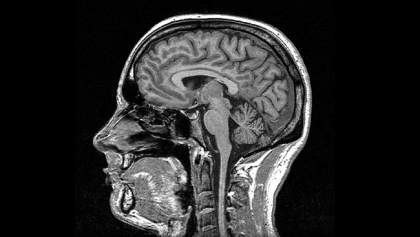

Produits de contraste pour scanner et IRM

Multi-G a développé la première gamme de produits de contraste pour scanner et IRM génériques.

Nous mettons ainsi à disposition des centres d'imagerie médicale en Afrique des produits de qualité à moindre coût, répondant ainsi au besoin croissant de diagnostic avancé pour un meilleure prise en charge des patients et des traitements plus efficaces. Dans un contexte où le patient a souvent la charge complète du coût du traitement, les produits de contraste Multi-G rendent les les soins accessibles à un plus grand nombre, et permettent aux centres d'imagerie de développer leur patientèle.